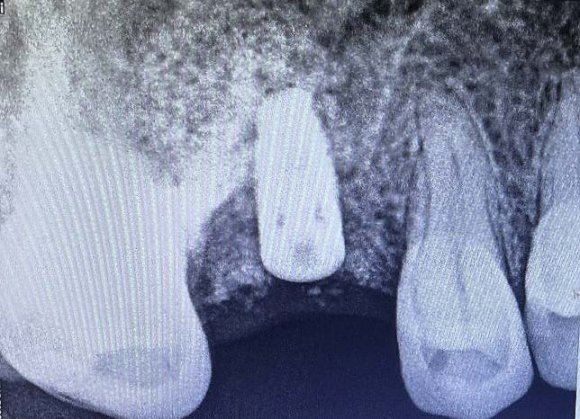

The patient was recalled after 10 days and then 3 months later. The soft tissue confirmed no inflammation and satisfactory wound healing. The radiographic analysis verified the densification of the xenograft and the osseointegration of the implant (Figure 5).